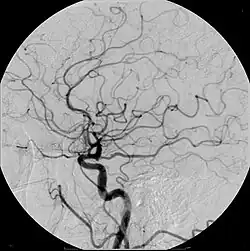

Um angiograma cerebral contrastado.

Os exames de contraste resolvem este problema. O paciente ingere uma solução com um determinado composto radioativo com uma curta meia-vida, o tecido que se deseja analisar absorve esta substancia a acaba “contrastando” em exames de ressonância, o que permite um diagnóstico médico. Este método é aplicado para exames de tireoide (o radiocomposto usado é o Iodo-131), próstata, intestino, dentre outros. Há também a produção de pasta de Bário, utilizada em seções de radioterapias para o tratamento de câncer.